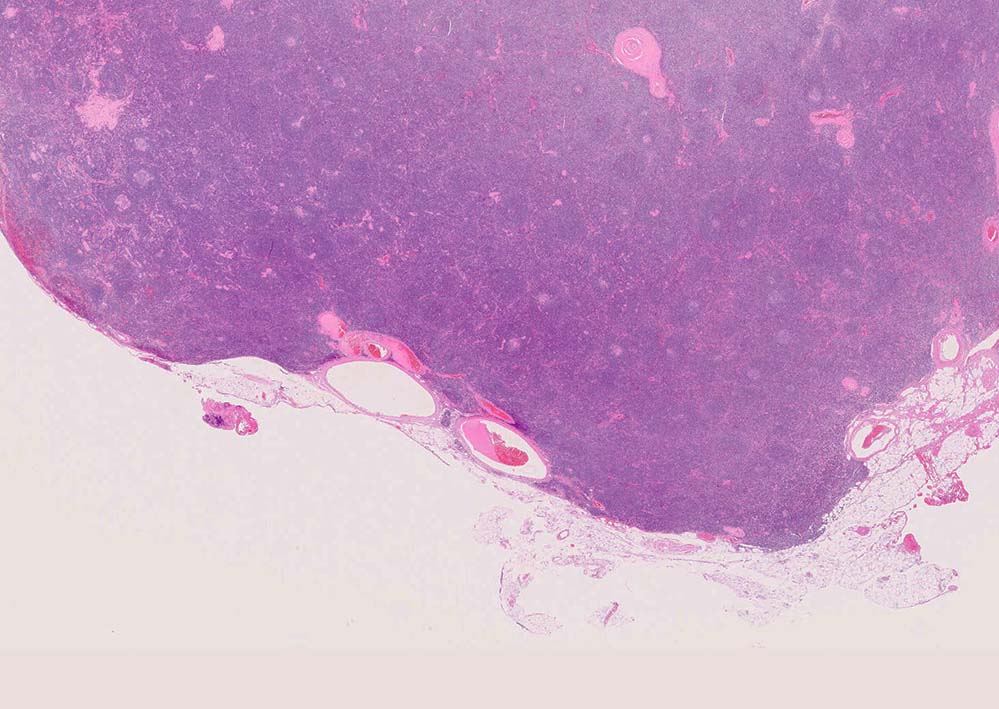

Castleman diseaseの病理

局所型CDの90%はHV type, 10%がPC type.

硝子血管型 hyaline vascular type: 臨床症状に関係なく3つの病理組織所見で診断が決まる。*1

1. 萎縮した胚中心をもつ異常な血管増生を示すリンパ濾胞(Lolli-pop follicles. Lolli-popはキャンディ-の名前のようです)

2. 濾胞間リンパ組織の線維化, 血管増生

3. 被膜は肥厚し, 少なくとも病変中心部ではsinuses(リンパ洞)を欠いている

我が国の教科書には, HV type Castleman diseaseに関して主に上記 1,2の組織所見についてしか記載がないものがほとんどであるが, 実は非常に多彩な組織像を呈する. (Dr.小島)

「広いmantle zoneの取り巻いたリンパ球の少ないFDCのめだつ小さな濾胞, 硝子化することもある, 濾胞間は細血管でいっぱい」がkey word